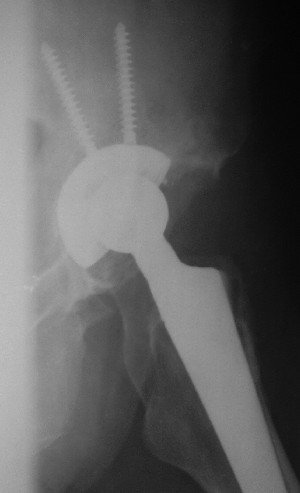

После протезирования прямой 5/04/04

После протезирования боковой 5/04/04

Больной 18 мая 2003 года в автоаварии получил перелом левой вертлужной впадины, вывих бедра. Госпитализирован в один из стационаров области.Вывих вправлен. В последствии бедро вывихивалось еще дважды. На консультацию был представлен снимок от 19.05.03г., больной переведен к нам 3.06.03г. Снимок при поступлении - перелом впадины, задне-верхний вывих бедра. 05.06.2003 г. выполнено открытое вправление вывиха левого бедра и остеосинтез стенки вертлужной впадины двумя винтами. Послеоперационный период без осложнений. Объем движений в левом тазобедренном суставе восстановился полностью. Выписан на амбулаторное лечение в удовлетворительном состоянии с рекомендациями 3 месяца ходить на костылях без нагрузки на оперированную конечность. На контрольных рентгенограммах левого тазобедренного сустава 13.10.2003 г. - признаки консолидации перелома; плотность, форма головки и состояние суставных поверхностей удовлетворительные. Разрешена дозированная осевая нагрузка, на конечность с использованием дополнительной опоры. 19.12.2003 г. больной обратился с жалобами на боли в левом тазобедренном суставе. На рентгенограммах левого тазобедренного сустава 19.12.2003 г., 20.02.04г. - асептичекий некроз головки бедра. 5.04.04г. - эндопротез. Сейчас ходит без трости, не хромает. Особенность эндопротезирования - при удалении винтов прослежена линия перелома заднего края впадины и предложено установить чашку несколько меньшего диаметра, чтобы она была покрыта несломанной частью.